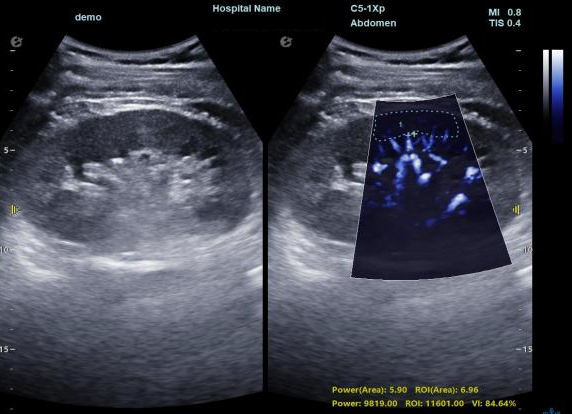

3) 通过血管指数(VI)定量评估局部血管密度,以定量化数据实时监测血流灌注情况,预判肾功能恢复情况;

开启肾移植微观视界 | 银河官网黑科技为您“移”路护航(图6)

超微视血流显像显示肾脏五级血管

开启肾移植微观视界 | 银河官网黑科技为您“移”路护航(图7)

微米级超高分辨率血流信号显像

开启肾移植微观视界 | 银河官网黑科技为您“移”路护航(图8)

肾脏的灌注评估,RI/VI量化数据

开启肾移植微观视界 | 银河官网黑科技为您“移”路护航(图9)

开启肾移植微观视界 | 银河官网黑科技为您“移”路护航(图10)

开启肾移植微观视界 | 银河官网黑科技为您“移”路护航(图11)

超微视血流显像评估肾移植术后灌注情况